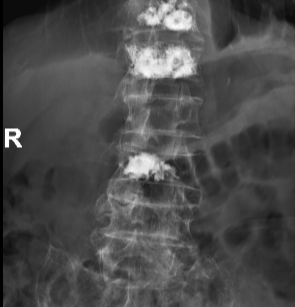

术后

李伯随即转入骨科治疗,张勇华副院长、骨科主任带领的骨科团队经讨论,详细制定手术方案并征得家属同意,决定尽快为李伯进行“经皮穿刺椎体成形术”,手术由李竖飞、林勇医生完成,手术顺利,术后2小时腰背部疼痛明显缓解,第二天李伯便可戴腰围下地行走,很快顺利出院,精神状态及身体各方面恢复良好。00: